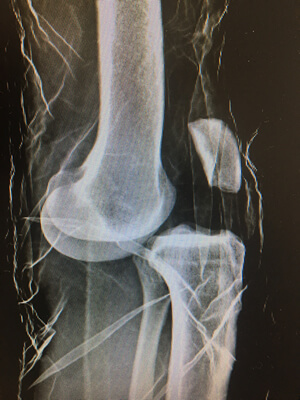

Radio d'une luxation du genou